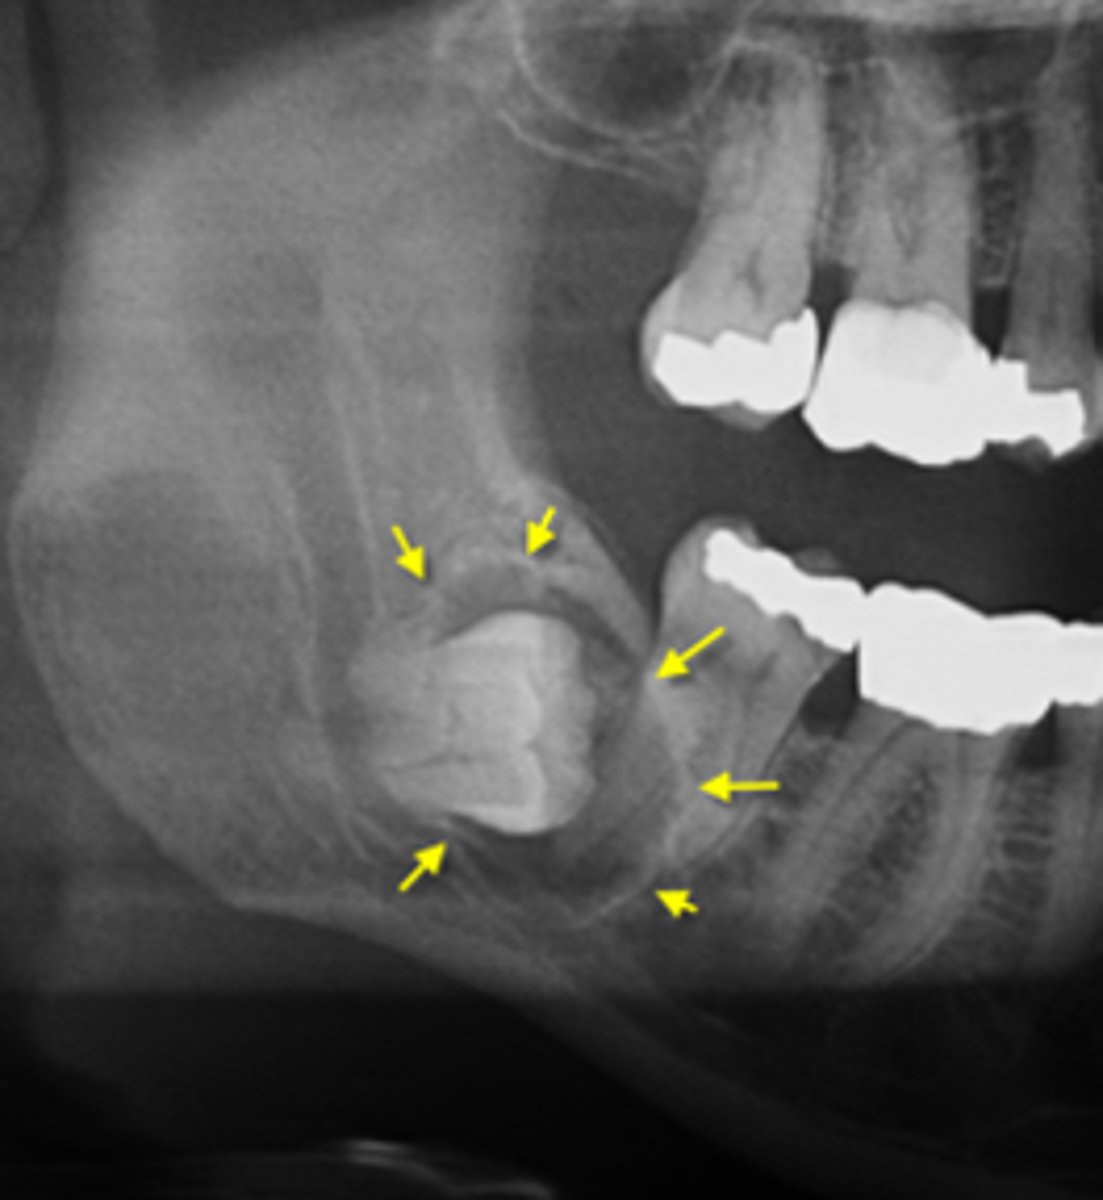

How would you describe the lesion?

- Well-defined corticated unilocular radiolucency in the left ramus causing expansion and thinning of

anterior and posterior walls of ramus, inferiorly below the inferior mandibular cortex and the coronoid process

- Dispalcement of the developing third molar.

What category would this lesion be part of?

Benign

What would be included in your D/D?

- OKC

- Unicystic ameloblastoma

- Dentigerous cyst